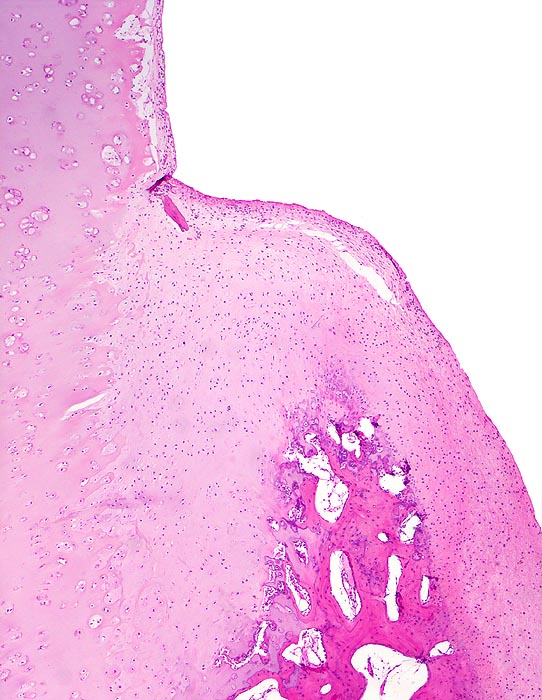

Coxarthrose: Randosteophyt

Knochen, Femurkopf

Übergang des residuellen hyalinen Gelenkknorpels in den Randosteophyten bedeckt mit neugebildetem Knorpel. Letzterer besteht nicht aus vollwertigem, Kollagen II-haltigem Knorpel, sondern aus Typ I und II-Kollagen. Daraus resultiert eine verminderte Belastbarkeit dieser neuen Gelenkfläche.

74-jährige leicht adipöse Patientin mit Anlaufschmerz, belastungsabhängigem Schmerz und zunehmender Versteifung im Hüftgelenk. Im Röntgenbild des Hüftgelenks zeigen sich eine Gelenkspaltverschmälerung, subchondrale Osteolysen, Usuren und randständige Osteophyten.